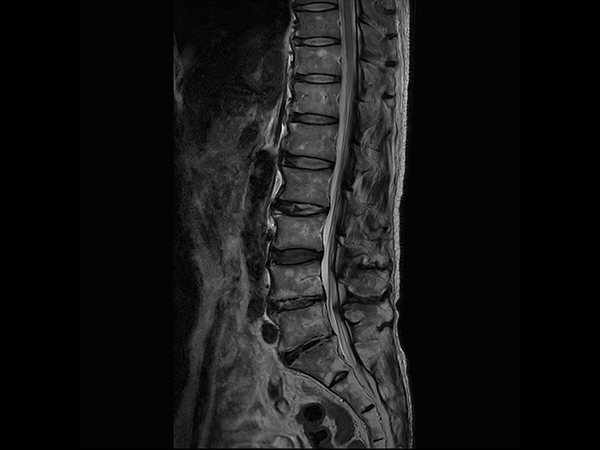

Sagittal T2w TSE